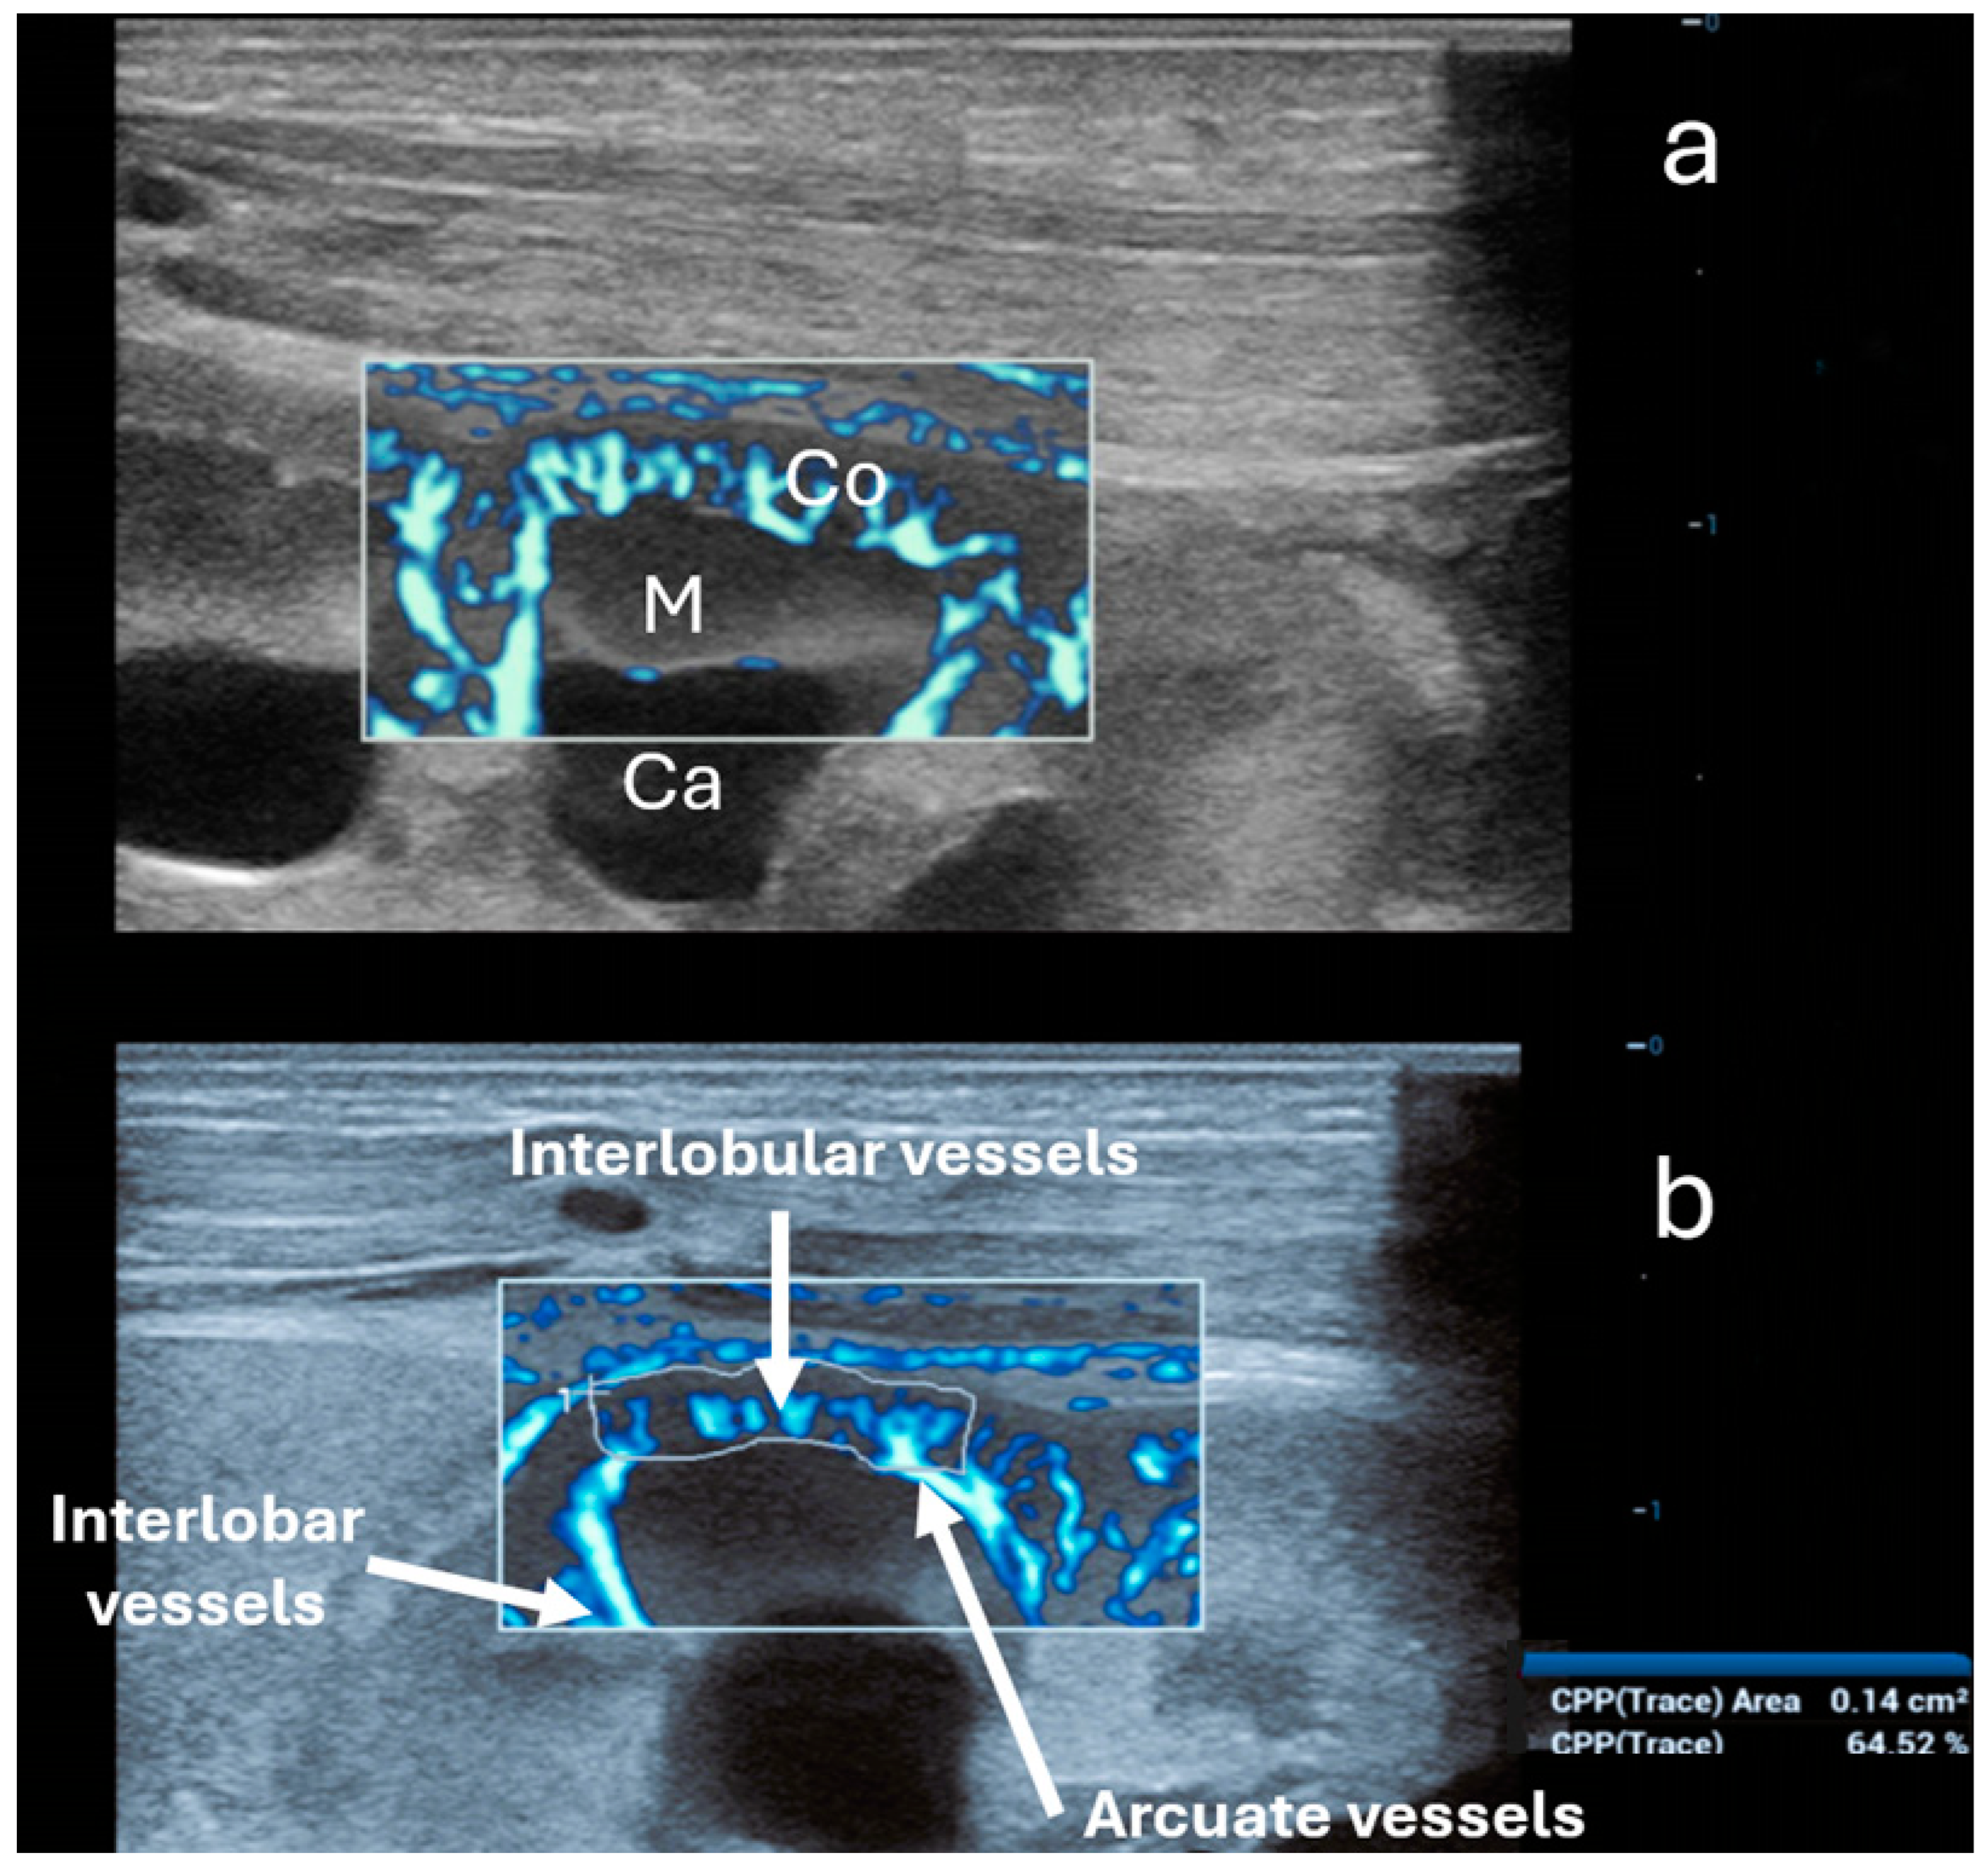

6. Ultra-Microangiography (UMA)